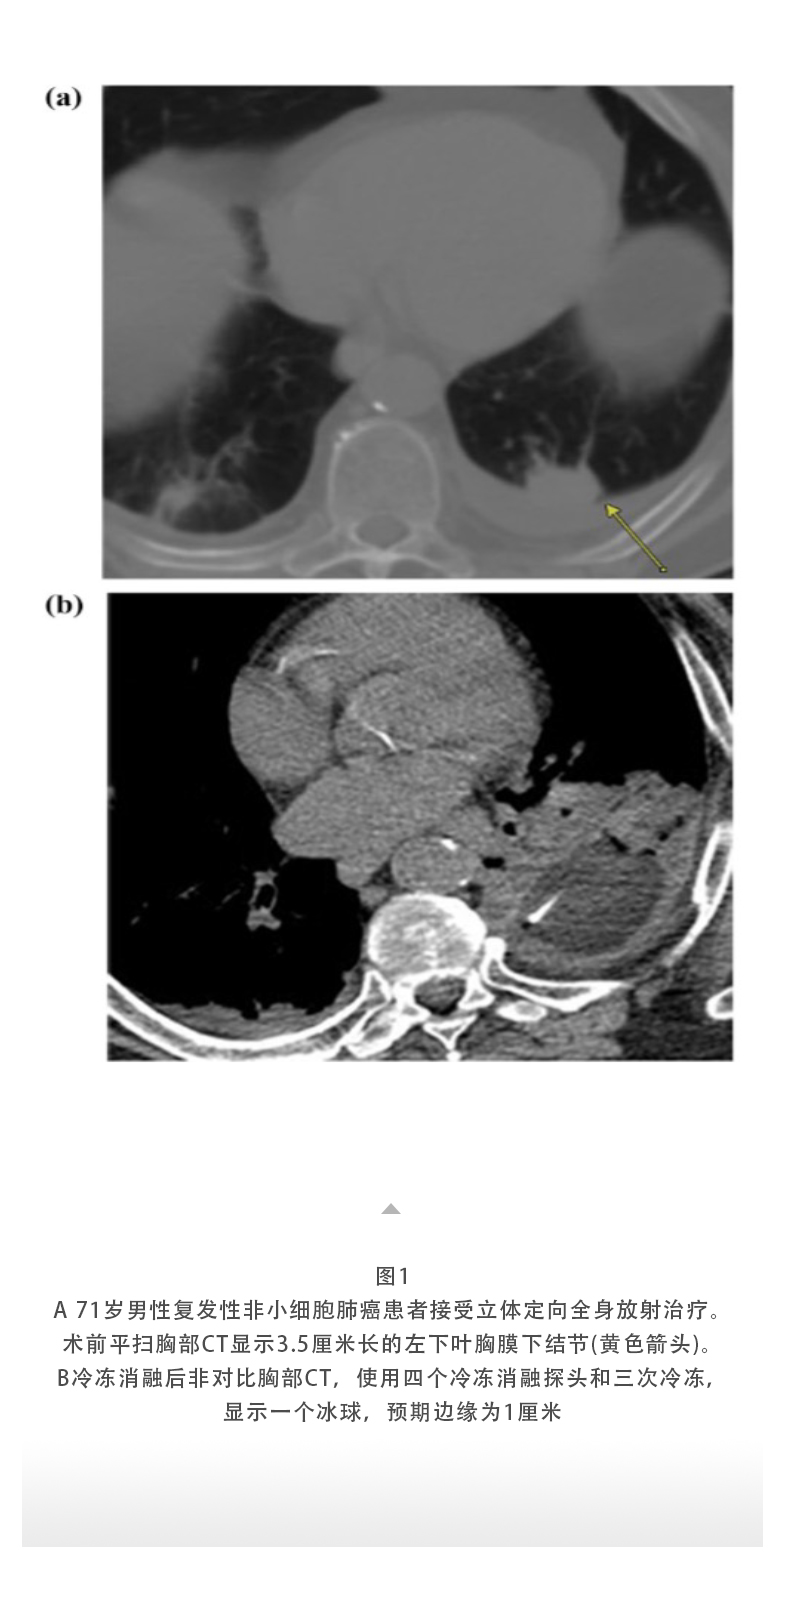

上一頁:【HYGEA·科研資訊】冷凍消融治療肺癌